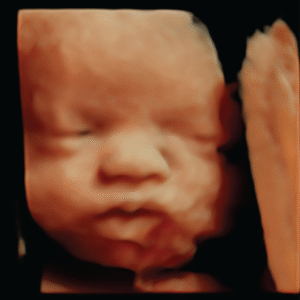

Explore our Photo Gallery and see the real results from Knit 4D Ultrasound. Every image you see  from 2D, 3D, 4D, to HD live ultrasounds  was captured by our highly trained team using our state-of-the-art ultrasound machine. We can begin creating amazing 3D/4D keepsake images as early as 8 weeks, giving you a beautiful first look at your baby.